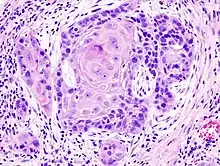

Carcinome épidermoïde

Un carcinome épidermoïde ou carcinome malpighien est un carcinome développé aux dépens d'un épithélium malpighien et pouvant atteindre un épithélium malpighien, paramalpighien ou glandulaire. Ce type de cancer peut être retrouvé au niveau de plusieurs organes et s'oppose classiquement à l'adénocarcinome qui se développe aux dépens d'un épithélium glandulaire.

Selon le degré de différenciation malpighienne, le carcinome épidermoïde peut-être peu, moyennement et bien différencié.